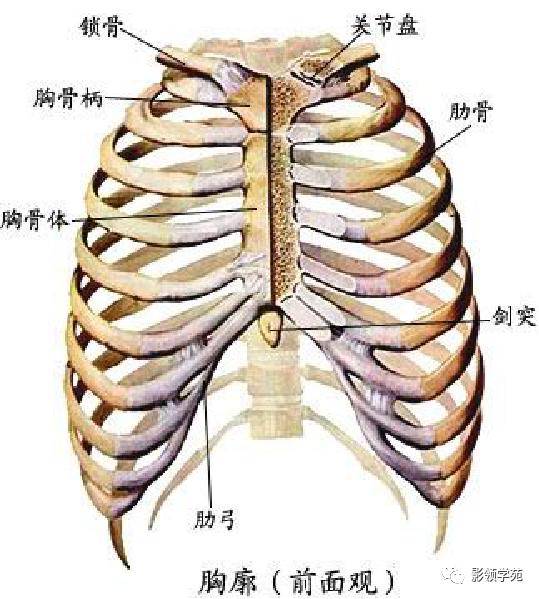

骨骼系统

骨骼系统